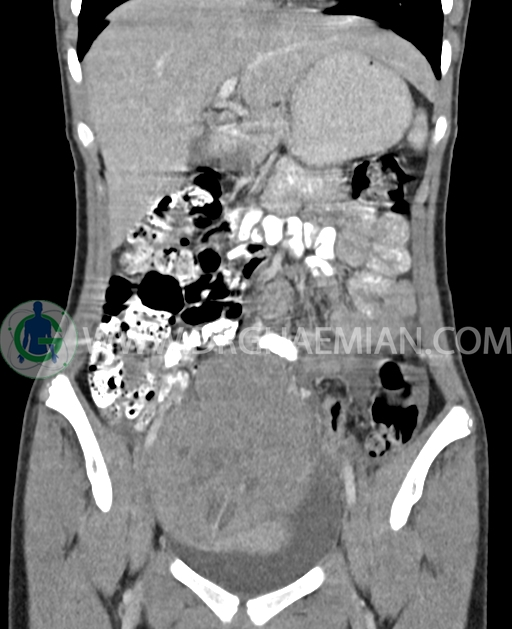

سی تی اسکن شکم و لگن از تشعشعات برای ایجاد تصاویر عرضی مقطعی از نایحه شکم و بین استخوان های لگن استفاده می کند. در این کیس تومور سلول زایا به ابعاد mm 125 x 112 x 80 دیده می شود.

در سی تی اسکن اسپیرال شکم و لگن با کنتراست خوراکی و وریدی (مولتی دیدکتور 16 با مقاطع ظریف و بازسازی های ساژیتال و کرونال) :

توده هیپردنس لوبوله بزرگ به ابعاد 125x112x80mm حاوی نواحی سیستیک داخلی و enhancement قابل توجه پریفرال همراه با آسیت متوسط در فضای شکم و لگن با احتمال بیشتر با منشا از تخمدان راست، درون لگن دیده می شود که در درجه اول مطرح کننده germ cell tumor می باشد .